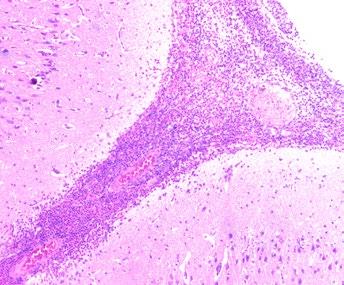

El estado del animal (Imagen 1).

IN VIVO

Es de gran interés tomar muestras de animales vivos con sintomatología característica, lo que permitirá un diagnóstico más amplio y representativo de la piara.

En este caso se seleccionarán muestras que no impliquen el sacrificio de los animales.

POST MÓRTEM

En caso de que haya bajas recientes de animales, se hará una necropsia reglada para poder obtener muestras de órganos o hisopados de los mismos.

Articulaciones sin abrir

Imagen 1. Ejemplos de toma de muestras en vivo vs post mórtem.